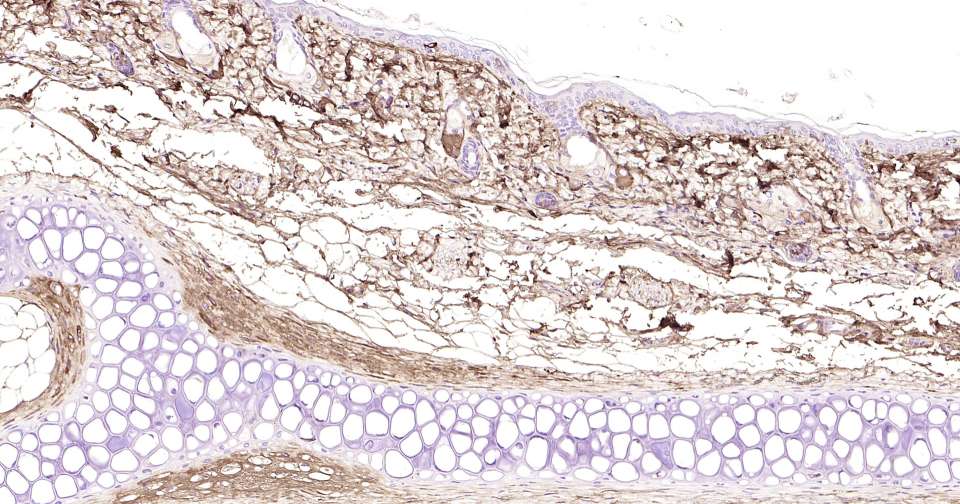

Immunohistochemical analysis of paraffin embedded rat skin tissue slide using IHC0401R (Rat Lumican IHC Kit).